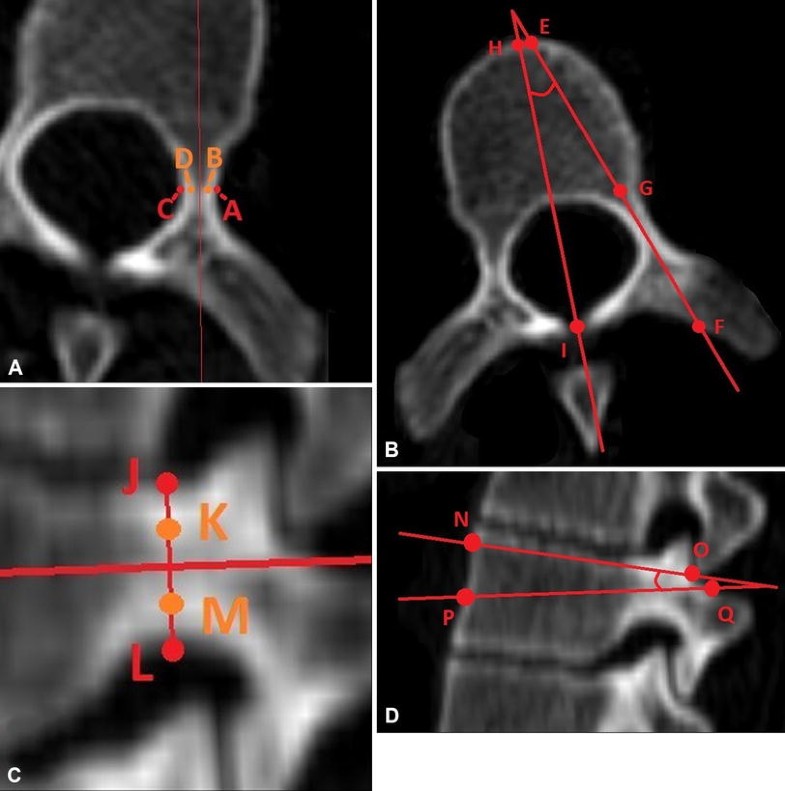

(A) This CT scan of a thoracic vertebrae in the local axial plane shows the outer cortical pedicle width (AC) and the inner cortical pedicle width (BD), where A is the lateral outer cortex margin, B is the lateral inner cortex margin, C is the medial outer cortex margin, and D is the medial inner cortex margin. (B) This scan of a thoracic vertebrae in the local axial plane shows chord length (EF), pedicle length (FG), and transverse pedicle angle (angle between EG and HI), where E is the anterior edge of the vertebral body along the pedicle axis, F is the posterior edge of the vertebra along the pedicle axis, G is a point in line with the posterior longitudinal ligament along the pedicle axis, H is the sagittal midvertebral line at the anterior aspect of the vertebral body, and I is the sagittal midvertebral line at the meeting of the laminae. (C) This CT scan of a thoracic vertebrae in the local sagittal plane shows the pedicle height (JL) and inner cortical pedicle height (KM), where J is the superior outer cortex margin, K is the superior inner cortex margin, L is the inferior outer cortex margin, and M is the inferior inner cortex margin. (D) This scan of a thoracic vertebrae in the local sagittal plane shows the sagittal pedicle angle (angle between the line NO and PQ), where NO is a line between the anterior (N) and posterior (O) aspects of the vertebrae angled midway between the superior and inferior endplates angles, while PQ is a line between the anterior (P) and posterior (Q) edges of the vertebrae along the pedicle axis in the sagittal viewing plane.